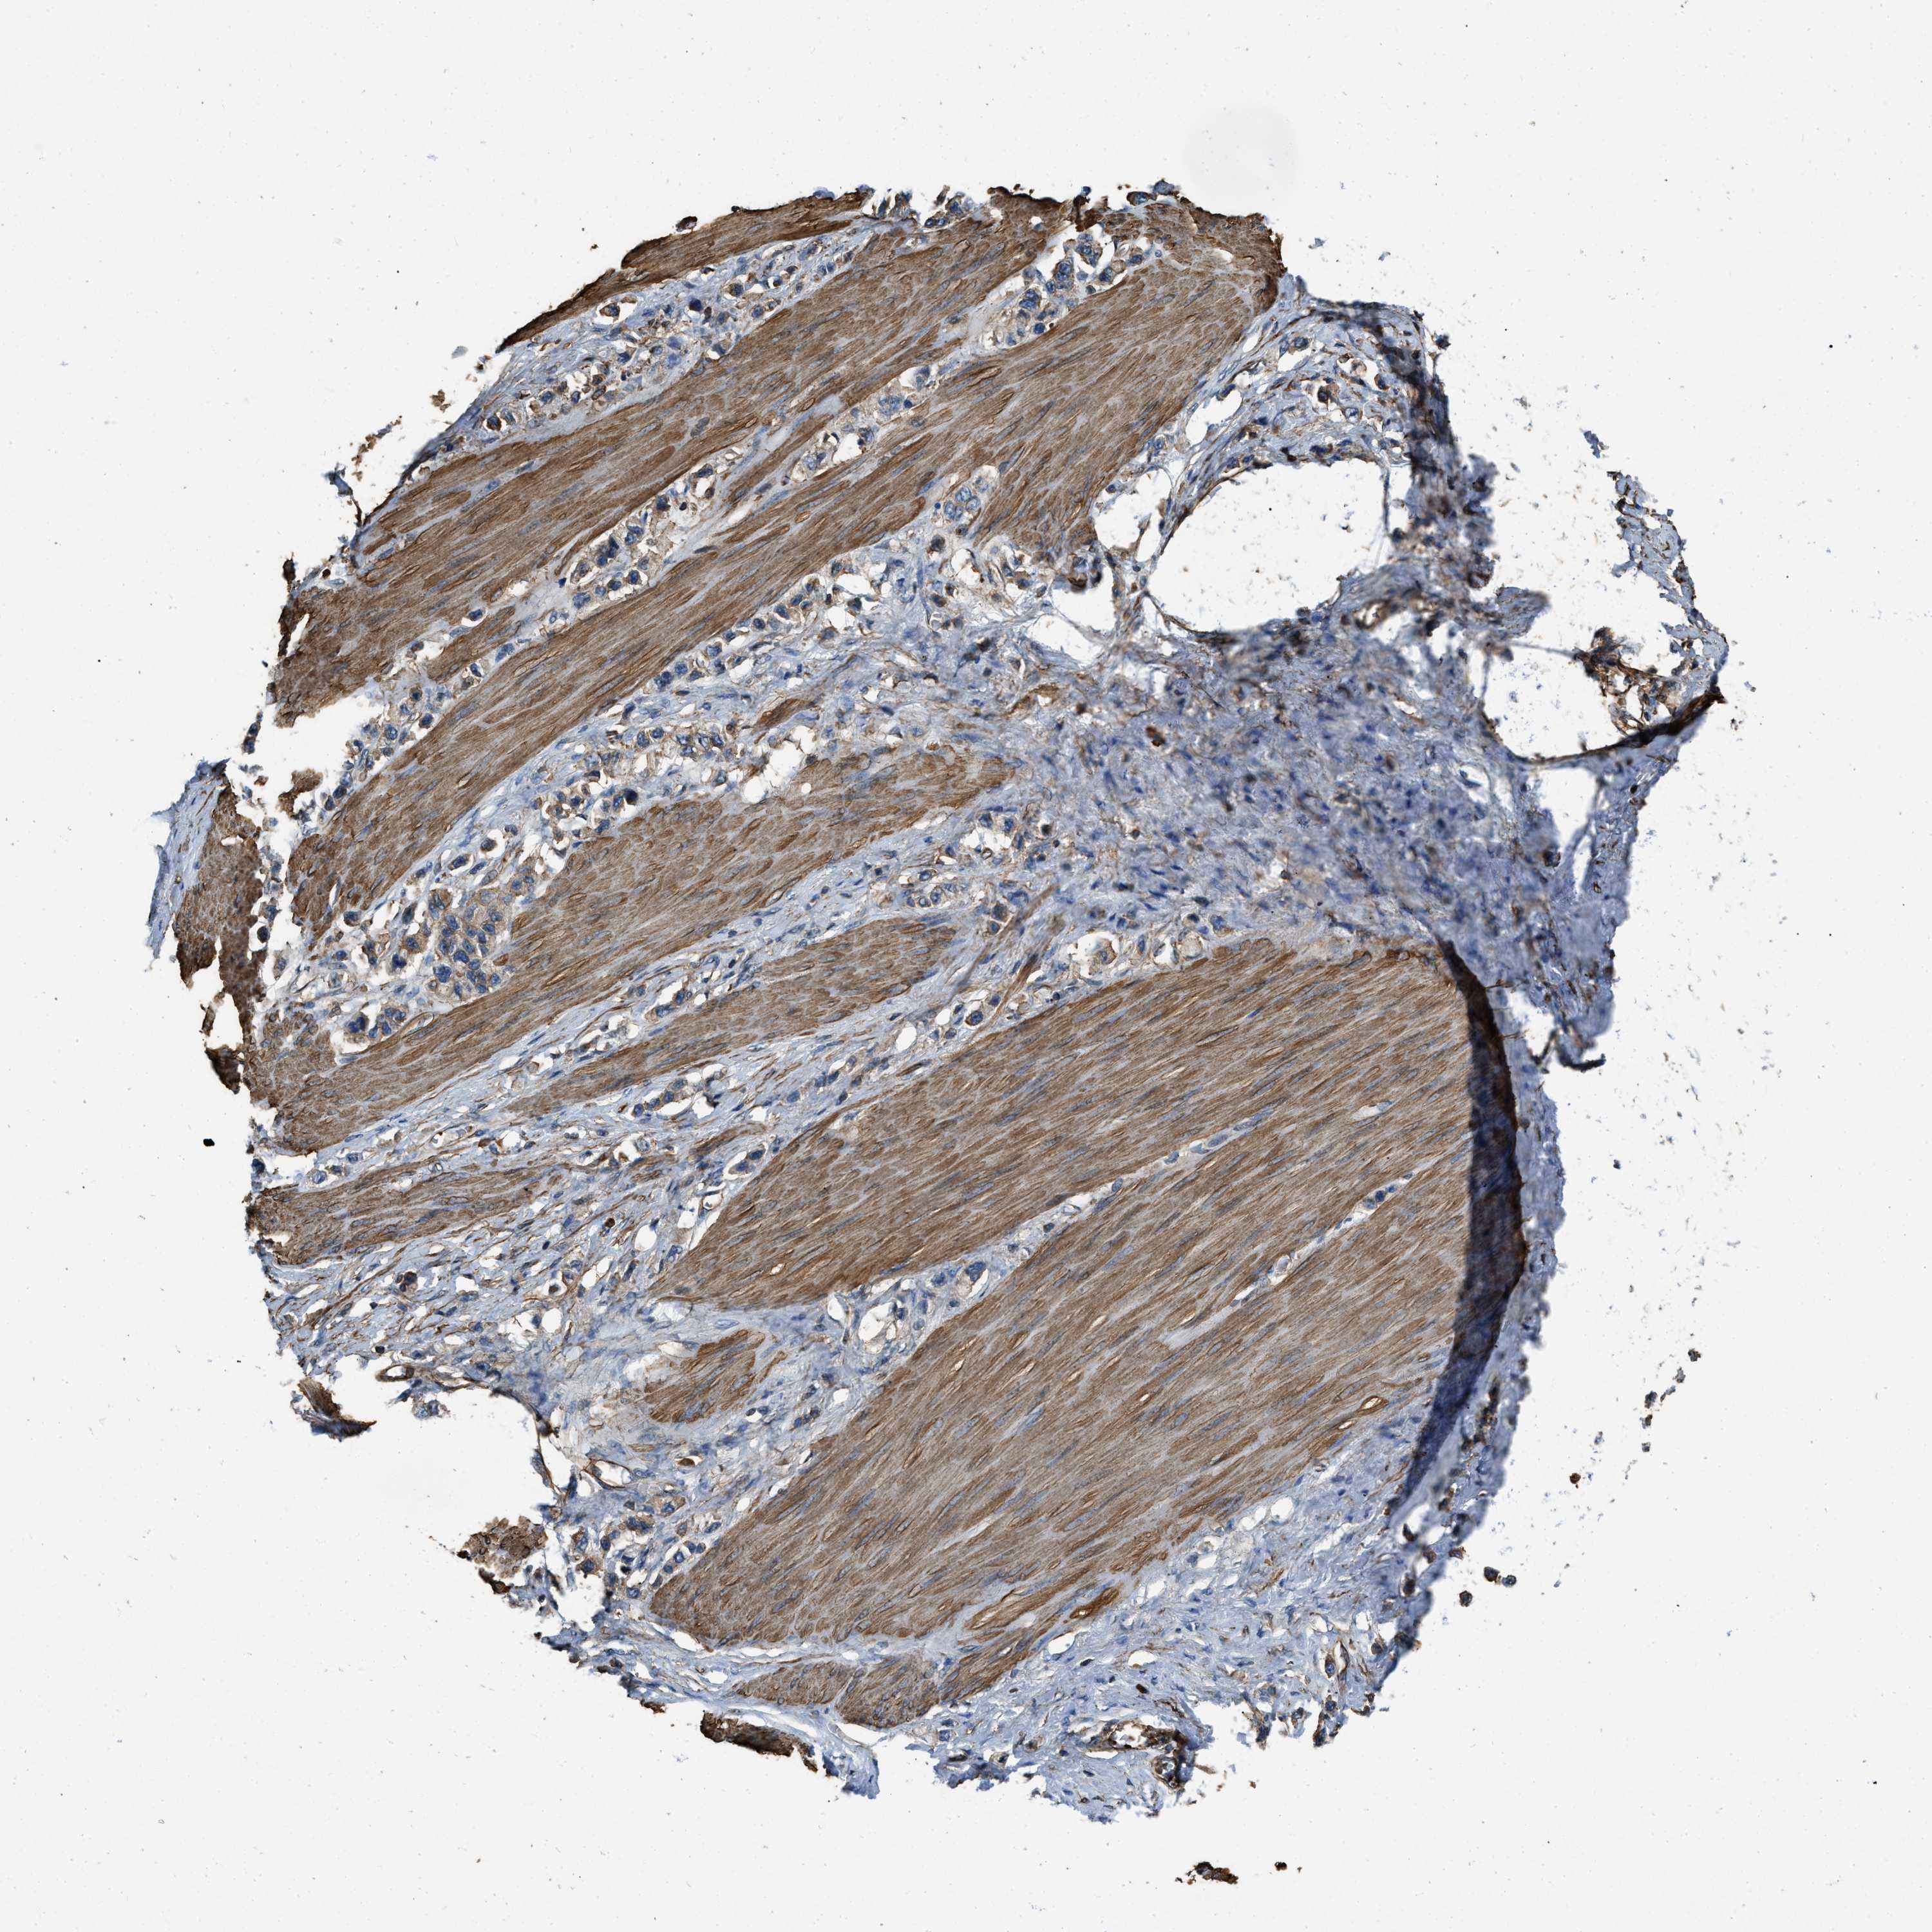

STOMACH CANCER - Protein expressioni

A mouse-over function shows sample information and annotation data. Click on an image to view it in a full screen mode. Samples can be filtered based on level of antibody staining by selecting one or several of the following categories: high, medium, low and not detected. The assay and annotation is described here.

Note that samples used for immunohistochemistry by the Human Protein Atlas do not correspond to samples in the TCGA dataset.

Antibody stainingi

Antibody staining in the annotated cell types in the current human tissue is reported as not detected, low, medium, or high, based on conventional immunohistochemistry profiling in selected tissues. This score is based on the combination of the staining intensity and fraction of stained cells.

Each image is clickable and will lead to virtual microscopy that enables deeper exploration of all samples and also displays staining intensity scores, fraction scores and subcellular localization as well as patient and tissue information for each sample.

Antibody HPA017936

Antibody HPA018950

Antibody HPA018954

Staining

High

Medium

Low

Not detected

Intensity

Strong

Moderate

Weak

Negative

Quantity

>75%

75%-25%

<25%

None

Location

Nuclear

Cytoplasmic/membranous

Cytoplasmic/membranous,nuclear

Adenocarcinoma, NOS